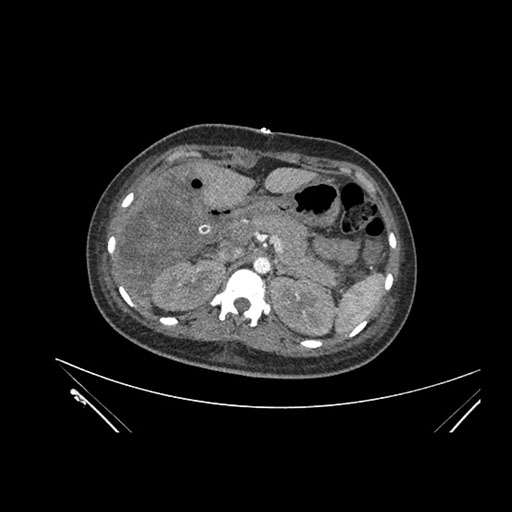

Imaging Analysis

Look through the patient's CT scan to identify any areas of concern for the necessary procedure.

Axial Arterial

Based on initial findings, which issue(s) would you be most concerned about?